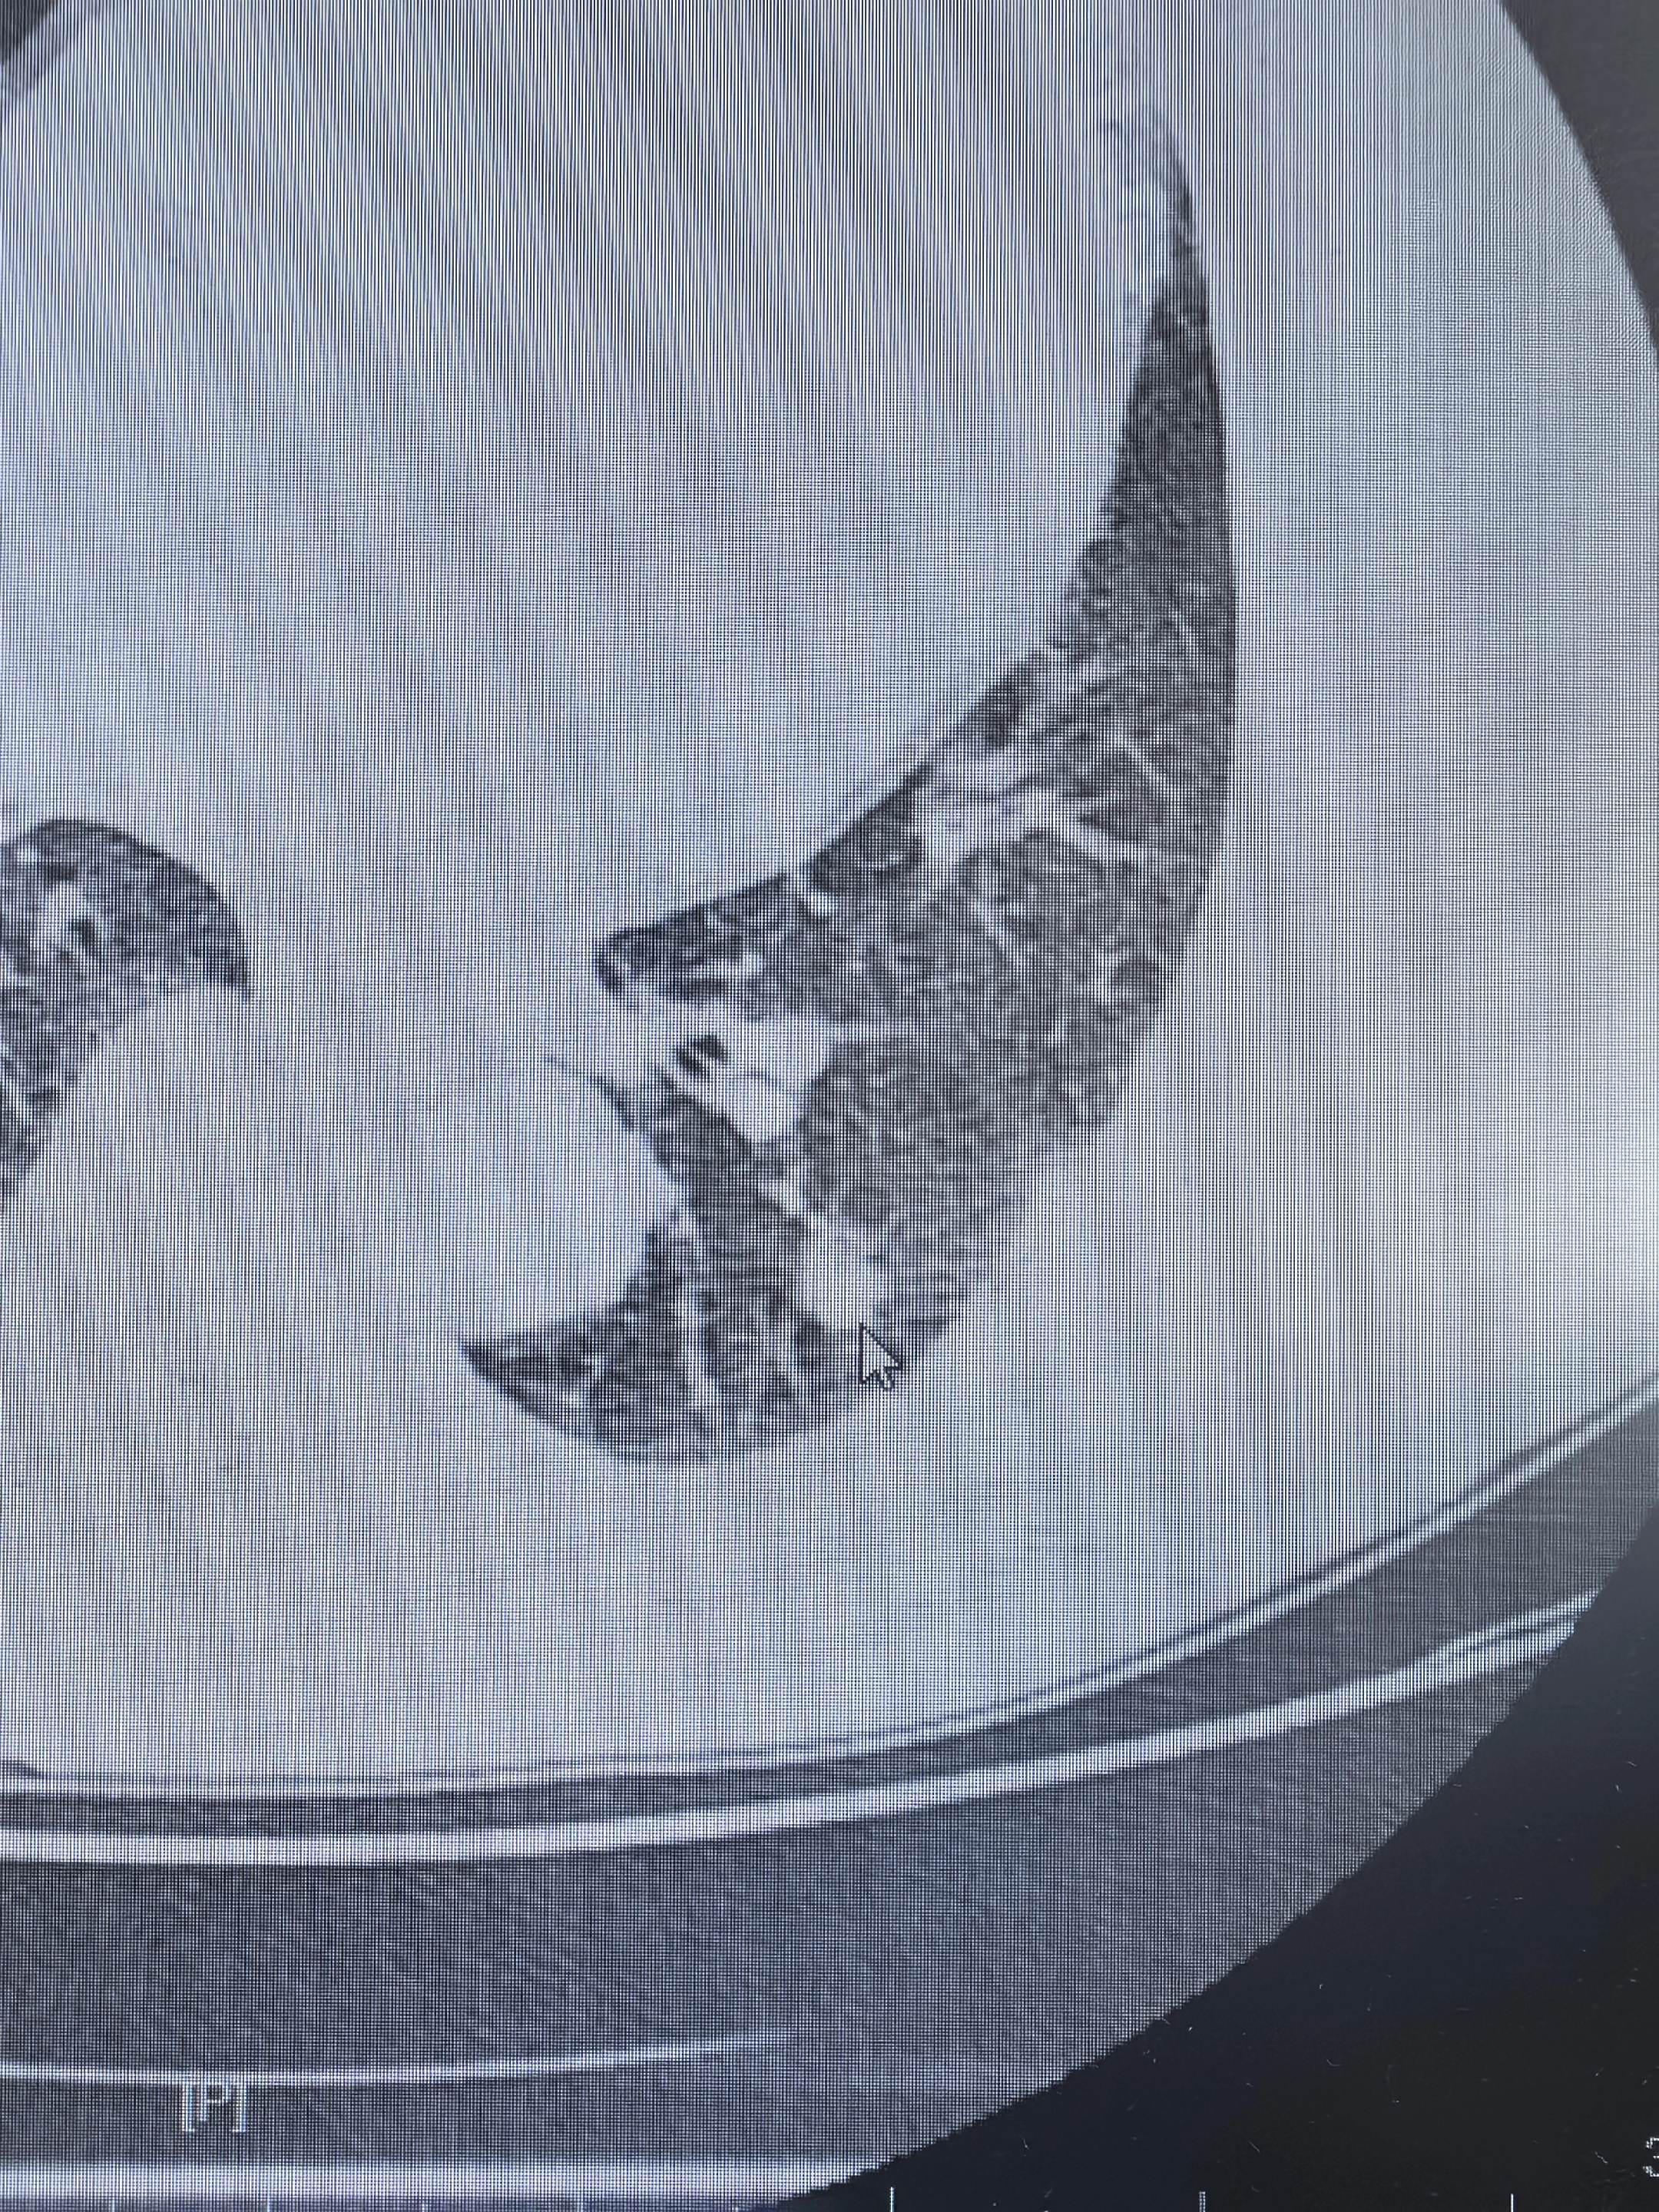

早期肺癌手术相对简单,我们也应该关注切口。早期磨玻璃结节类型的肺癌手术的效果几乎都是根治,对于一些比较简单的手术我们团队会把切口做的很小,这个美容切口的缝合方法也是借鉴了很多大中心的经验……

比如今天复查的这个病人,既然手术简单,就把创伤降到最低吧……